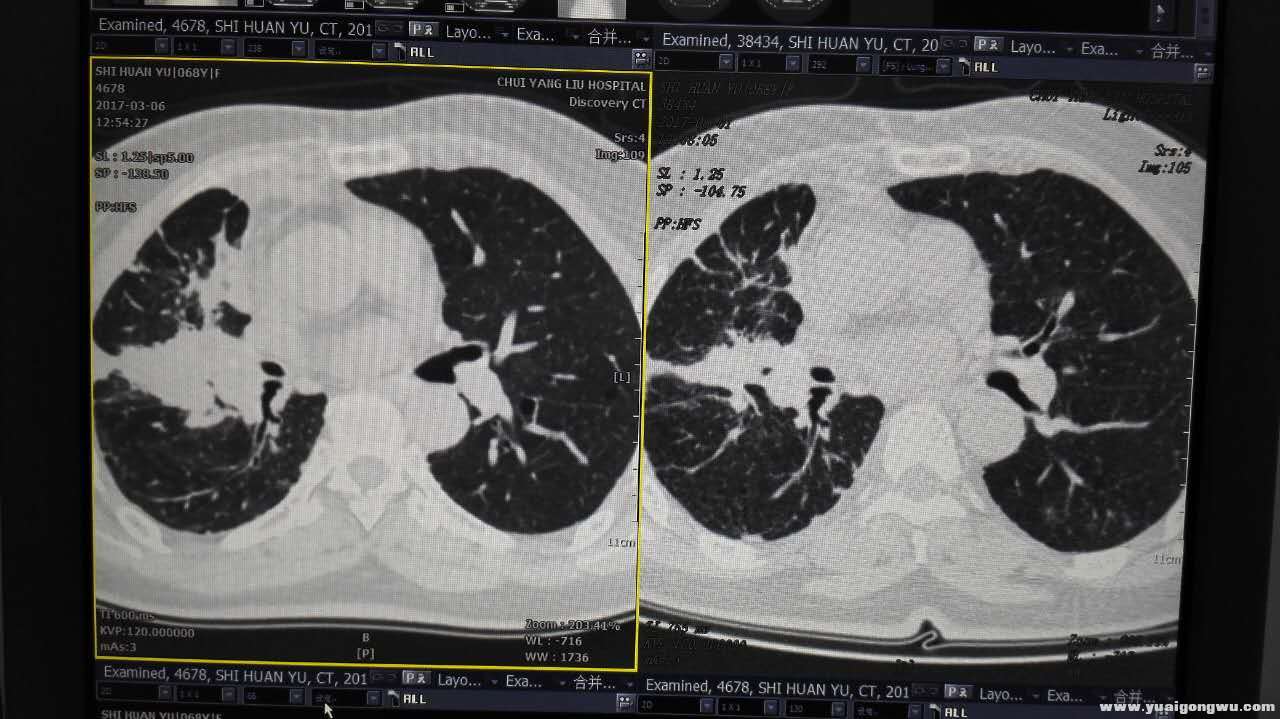

2017年6月1日,是我妈妈采用吉西他滨减量节拍化疗方案的三个月,汇报一下我妈妈这三个月吉西他滨节拍化疗的效果:2017年3月10日开始化疗前的CEA为203.4,第一个月吉西他滨节拍化疗(每周一次,共四次),4月7日的CEA降到121.7(降幅40%);第二个月吉西他滨节拍化疗(一个月三次,减少一次),5月5日测的CEA为42.86(降幅65%);第三个月吉西他滨节拍化疗(仍然一个月三次),6月1日检测CEA为21.86(降幅49%),从最初三个月前的203.4下降到21.86,累积降幅89%,今天的CT影像也显示原发肿块明显缩小,炎症性病变减少很多。为了给脊髓细胞提供休养生息的时间,下一阶段我准备采用以前有效的的2992联合1120方案。后面几张图片是我今天在影像科拍的3月5日的CT和6月1日的同层CT对比图,左边为3月5日的影像,右边为6月1日的影像。

2.jpg 5.jpg 8.jpg 10.jpg